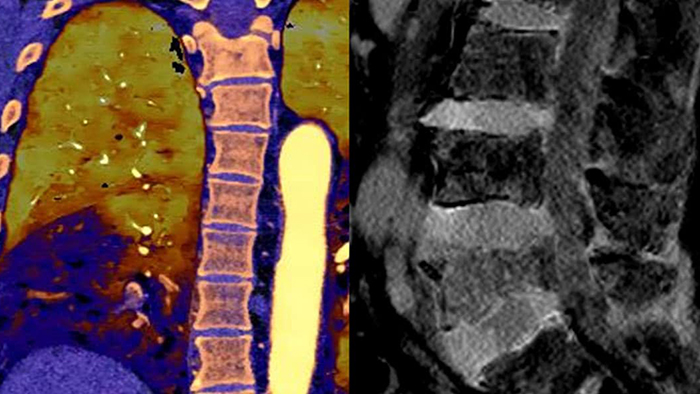

CT-Systeme mit Spektraldetektor machten konventionelles CT zu quantitativem CT. Die zweite Generation des Philips Spectral CT 7500 erhielt den Aunt Minnie Award for Best New Radiology Device in 2021.

Im Gegensatz zur klassischen CT-Untersuchung beinhalten Spektraldetektor-CT-Daten immer auch spektrale Informationen, ohne spezielle Vorkehrungen oder zusätzliche Vorbereitungen. Das bedeutet, Sie können die Spektraldaten jeder Untersuchung auch retrospektiv mit unterschiedlichen Diagnosetools analysieren. Sie können beispielsweise die monoenergetischen Energielevel anpassen oder Z-effektive Bilder erhalten.

Spektralergebnisse – jederzeit und überall. Eine einzelne DICOM-Entität enthält ausreichende Informationen für die retrospektive Analyse.